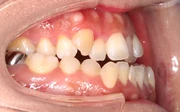

上下のガタガタが著しく八重歯が目立ち、見た目も歯磨きもしにくいという悩みを持った患者さま。4本の小臼歯抜歯を行い、17ヶ月という治療期間を経て、かみ合わせとスマイル時の見た目が改善しました。

難しいケース2.上顎前突(出っ歯)

上の前歯や上顎が大きく前にでているかみ合わせ。口元が出ていて、出っ歯を治したいという希望の患者さま。23ヶ月という治療期間を経てかみ合わせと口元が改善しました。

難しいケース3.下顎前突(反対咬合・受け口)

下の前歯や下顎が上の前歯よりも前にでているかみ合わせ。受け口が子供の頃よりコンプレックスで目立たない装置での治療を希望された患者さま。22ヶ月という治療期間を経てかみ合わせと口元が改善しました。